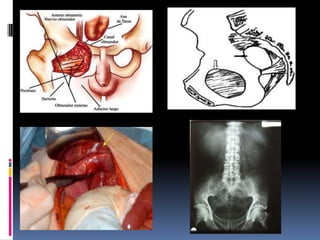

HERNIA OBTURATRIZ

Es la protrusión de contenido abdominal a

través del orificio obturador de la

pelvis, preferentemente en el lado derecho.

Son excepcionales y la mayoría de cirujanos

verán pocas a lo largo de su carrera.

Son más frecuencia en mujeres mayores

delgadas y multíparas.

La incidencia es superior en países asiáticos, por